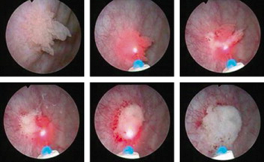

Tumor de vejiga:

Los tumores de vejiga son lesiones que requieren extirpación, el método más habitual es la resección endoscópica mediante energía monopolar o bipolar, lo cual permite la extirpación en fragmentos del tumor para realizar el estudio anatomopatológico e identificar el tipo de lesión y profundidad de la misma. Recientemente se está estudiando un tipo de resección diferente denominada resección en bloque, con lo cual se extirpa todo el tumor en su totalidad y no en fragmentos, con lo que se consigue un análisis más certero de la pieza quirúrgica, siendo una de las herramientas estudiadas el láser, con lo cual se puede conseguir la extirpación en bloque antes mencionada, sin embargo este procedimiento aún está en estudio, por lo cual aún no está estandarizado.